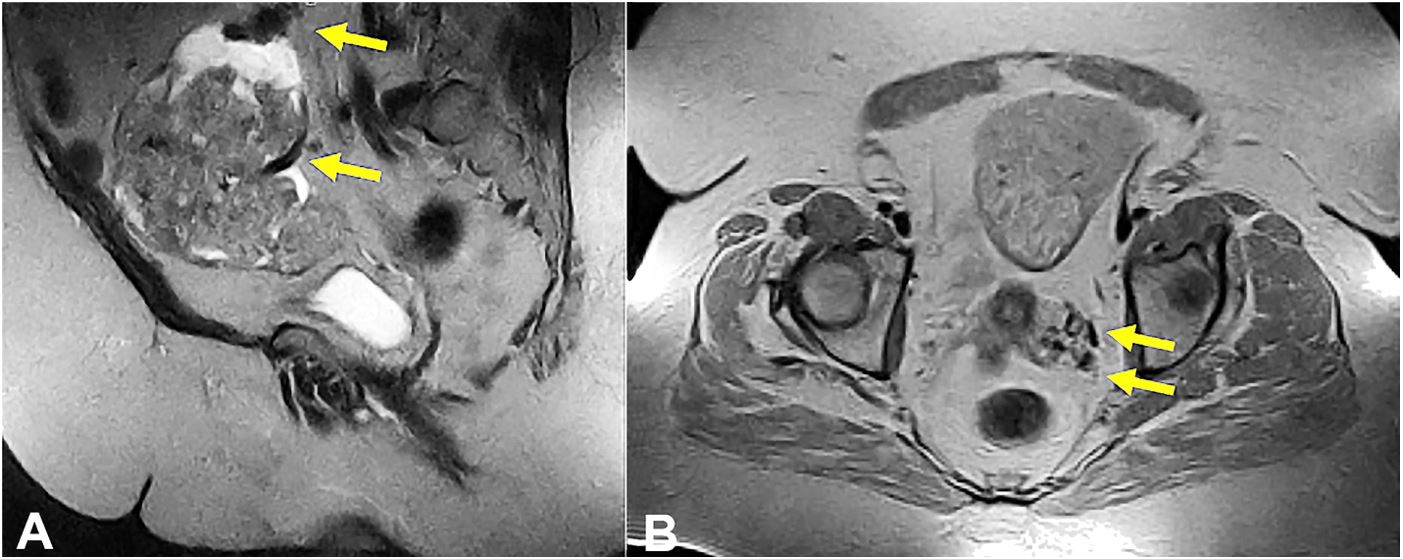

She was previously hospitalized at an outside institution for severe anemia requiring 8 units of red blood cells transfusions three months prior to the surgery. Pelvic ultrasound visualized an enlarged (16 cm) uterus with an 11 cm right-sided fundal mass and 3-mm-thickened endometrium. Follow up magnetic resonance imaging (MRI) re-demonstrated the 11 cm heterogeneous isointense and hyperintense solid mass with peripheral cystic regions concerning for leiomyosarcoma or a degenerating fibroid (Figure 1A). There were multiple smaller isointense and heterogeneous hyperintense uterine masses including a 4.1 cm heterogeneous cervical mass. Multiple endometrial biopsies were negative for hyperplasia or malignancies. While outside workup was inconclusive for the etiology of her bleeding, she was treated with Megestrol Acetate with incomplete resolution of her symptoms.

Hysterectomy with intraoperative consultation was pursued due to a high clinical suspicion of a malignant process. Procedural imaging findings revealed a large uterine mass perfused by perforator feeder vessels invading into the retroperitoneal space along with an irregular cervical mass heavily interlaced with uterine vessels (Figure 1B).